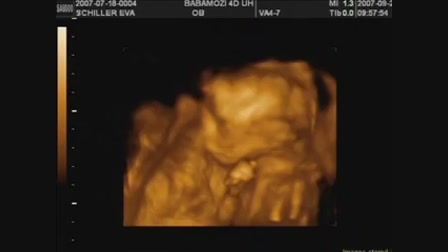

Lau németül tanul, íme a fejlődés... :)